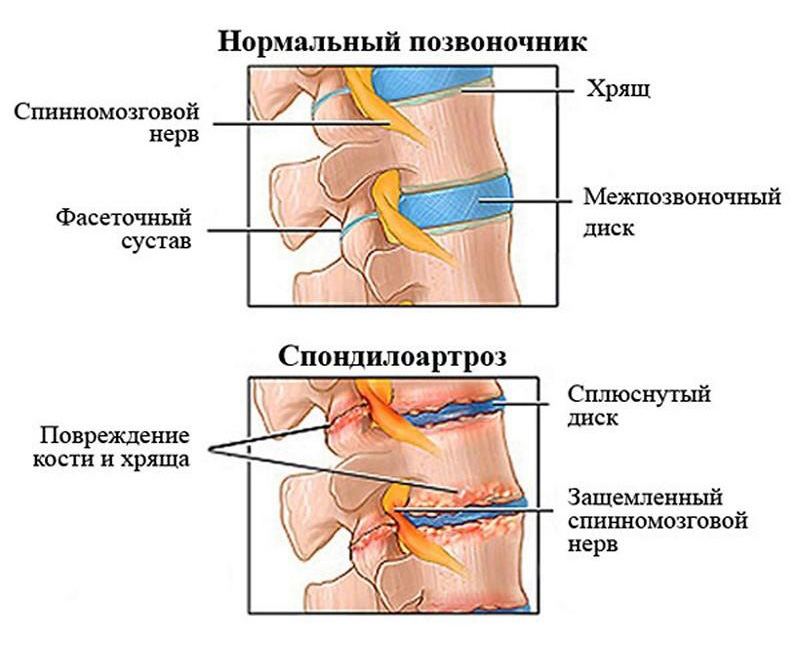

КТ-протрузии дисков: Визуализация и классификация